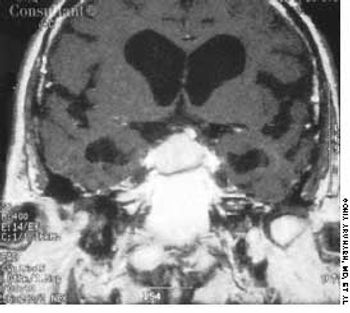

A 40-year-old woman with a history of amenorrhea complained of recent headaches and galactorrhea for the last 6 months. A neurologic work-up revealed bitemporal hemianopia, and a radiograph of the skull suggested an enlarged sella turcica. A large pituitary adenoma disclosed by an MRI and a serum prolactin level of 360 µg/L led to a diagnosis of prolactinoma.